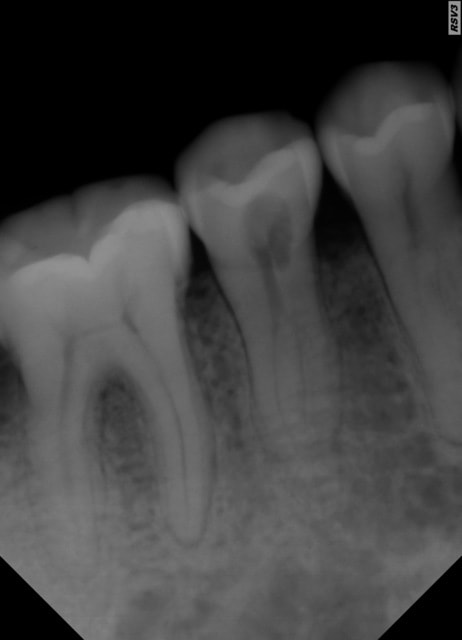

La radio de 45 révèle une carie ??? mais en bouche pas de point d'entrée, et le test de vitalité est positif mais pas douloureux.

amha, la 45 présente une résorption interne et/ou externe

après la rétro de ta 45 montre une belle lésion, et même si ta 45 répond encore au froid, tu peux avoir une nécrose partielle surtout qu'on distingue bien deux canaux radiculaires dans ta 45.

Personnellement, j'envisagerai l'endo de 45 en faisant bien attention à l'aspect de la pulpe (rouge vif ou sombre) et l'éxérèse de l'épulis qui pourrait à ce moment là être une manifestation d'une fistule dont l'origine serait 45 (canal latéral ou accessoire). Cette situtation serait alors maintenue en équilibre, ou en phase chronique depuis un bon moment.

Effectivement, il s'agit sans aucun doute d'une résorption externe. Je te déconseille de te lancer comme ça dans le traitement endo (déjà parce qu'il n'est pas nécessaire et qu'en plus, si tu supprimes la prédentine qu'il te reste entre la pulpe et la lésion externe, ça va saigner abondamment et tu ne pourra pas obturer dans la séance (avec suites opératoires ++ liées au fait que tu aura une extrusion de NaOCl vers la gencive).

Donc, chirurgie pour enlever l'excroissance gingivale, curetage de celle-ci jusqu'à la dentine de la 45, etching et verre iono. Puis, traitement endo si la dent perd sa vitalité ou devient symptomatique.

Ceci dit, il est vrai qu'un examen cone beam te donnerai une bonne idée de la destruction de la dent (pour classer cette résorption dans l'un des 4 stades) et ainsi savoir quel est le pronostic. (à mon avis elle est en stade 2...ou 3).